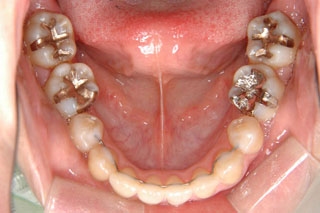

2年半ほどの治療で、装置を撤去し保定治療に移行しています。概ね緊密な臼歯の咬合と前歯の被蓋が確立されました。

保定治療を開始してから2年半が経過していますが、良好な咬合の安定が維持されています。見た目だけではなく、中心位マウントの咬合器にて顎位のズレを計測していますが、計測値は1mm未満の数値である事を確認しています。理想的には中心位=咬合位かも知れませんが、多少の遊びは必ず出てきます。しかしながら最初からルーズなゴールを目指していたら、的を外してしまうでしょう。できれば、ピンポイントで理想を目指したいものです。